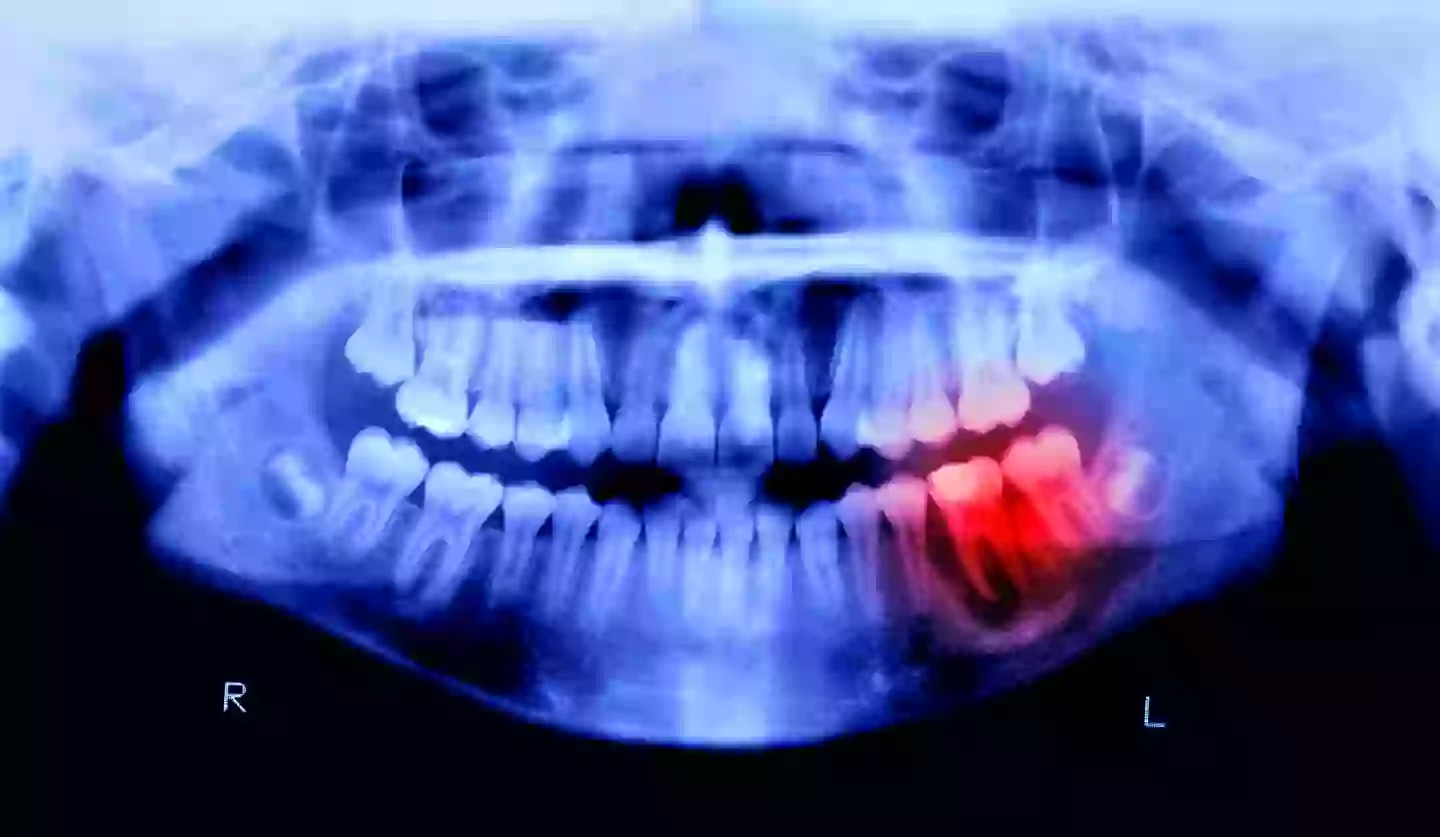

Could gum disease be linked to Alzheimer’s (Peter Dazeley/Getty)